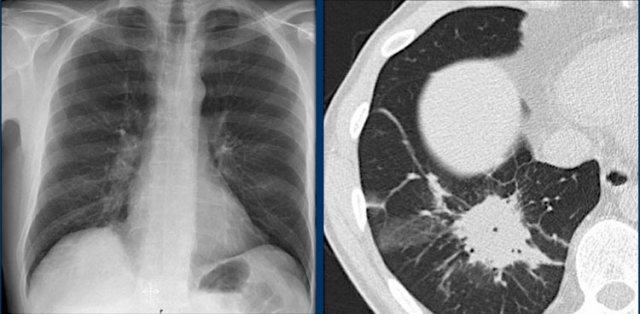

Tim và Màng Ngoài Tim

Bờ Tim trên X-quang Ngực Thẳng

Trên phim X-quang ngực thẳng tiêu chuẩn, chỉ có thể quan sát được bờ ngoài của tim. Trong hầu hết các trường hợp, chúng ta có thể đánh giá kích thước tổng thể của tim và bóng tim, nhưng việc đánh giá từng buồng tim riêng lẻ là khó khăn. Tuy nhiên, hiểu biết về vị trí giải phẫu của các buồng tim giúp ích cho việc phân tích các thay đổi về hình dạng và bờ tim liên quan đến giãn buồng tim.

Nhĩ Trái (NT)

Đây là buồng tim nằm sau nhất, nhận máu đã được oxy hóa từ các tĩnh mạch phổi đổ vào nhĩ trái theo hướng gần như nằm ngang. Tiểu nhĩ trái đôi khi có thể nhìn thấy như một phần lồi nhỏ ngay bên dưới thân động mạch phổi (thấy rõ nhất trên tư thế nghiêng).

Dấu hiệu X-quang của giãn nhĩ trái:

- Tư thế thẳng (PA): Phồng bờ tim phải phía trên và mở rộng góc carina do hai phế quản gốc bị đẩy ra hai bên.

- Tư thế nghiêng: Phồng bờ tim sau-trên.

Nhĩ Phải (NP)

Nhận máu thiếu oxy từ tĩnh mạch chủ trên và tĩnh mạch chủ dưới.

Dấu hiệu X-quang của giãn nhĩ phải:

- Tư thế thẳng (PA): Bờ tim phải bị đẩy ra ngoài.

Thất Trái (TT)

Nằm ở phía sau và bên trái so với thất phải.

Dấu hiệu X-quang của giãn thất trái:

- Tư thế thẳng (PA): Bóng tim mở rộng sang trái

- Tư thế nghiêng: Phồng bờ tim dưới-sau.

Thất Phải (TP)

Vị trí: Buồng tim nằm trước nhất, ngay sau xương ức.

Dấu hiệu X-quang của giãn thất phải:

- Tư thế thẳng (PA): Giãn có thể đẩy bóng tim sang trái, trong các trường hợp nặng, bờ tim trái có thể được tạo thành bởi thất phải.

- Tư thế nghiêng: Lấp đầy khoang sau xương ức tiến triển dần, bắt đầu từ phía dưới và lan lên trên khi thất phải giãn to hơn.

Bờ Từng Buồng Tim trên Tư Thế Nghiêng

- Nhĩ Trái: Tạo thành bờ tim sau-trên; giãn gây phồng ra phía sau.

- Thất Trái: Tạo thành bờ tim sau-dưới; giãn gây di lệch ra sau-dưới.

- Thất Phải: Chiếm khoang sau xương ức phía dưới; giãn lấp đầy khoang sáng sau xương ức theo hướng từ dưới lên trên.

Tương quan trên CT

Giải thích cho hình ảnh khuyết tim được thể hiện rõ trên ảnh CT này.

Ở mức ngang tim dưới, thùy dưới phổi phải (mũi tên xanh dương) thường kéo dài ra phía trước nhiều hơn thùy dưới phổi trái (mũi tên đỏ), lý giải cho sự bất đối xứng của khuyết tim.